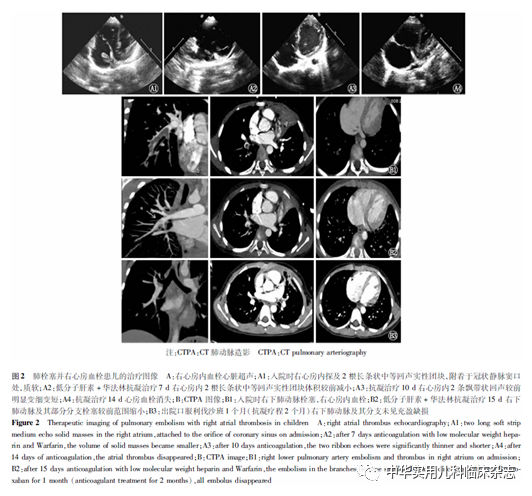

结果2.1 一般情况 30例患儿中男17例,女13例,男女比例为1.31∶1.00,年龄(8.95±2.58)岁(4~13岁),自发病至肺栓塞确诊时间(CTPA检查明确显示)为1~28 d[(12.8±6.1) d],其中6例(20.0%)在发病7 d内确诊,3例(10.0%)在发病2 d内确诊。抗凝疗程1~9个月,随访时间3~59个月。诊断年份2017年3例(10.0%),2018年3例(10.0%),2019年1例(3.3%),2020年6例(20.0%),2021年17例(56.7%)。2.2 临床特征 30例患儿病程中均伴咳嗽症状(100.0%),发热29例(96.7%),胸痛15例(50.0%),咯血9例(30.0%),4例(13.3%)无咯血表现但支气管镜检查发现血性分泌物,腹痛3例(10.0%),下肢疼痛4例(13.3%)。气促27例(90.0%),7例(23.3%)患儿经皮测血氧饱和度<0.95(0.90~0.95),给予鼻导管低流量吸氧,2例(6.7%)明显呼吸困难,血气分析 Ⅰ 型呼吸衰竭,给予呼吸机辅助呼吸及经鼻高流量氧疗。肾病综合征(NS)2例(6.7%),紫癜性肾炎(肾病综合征型)1例(3.3%),狼疮性肾炎(肾病综合征型)1例(3.3%),其中并抗磷脂抗体综合征1例(3.3%),先天性心脏病(房间隔缺损)1例(3.3%),遗传性蛋白S缺乏症(PSD)1例(3.3%),骨髓炎1例(3.3%)。2.3 实验室检查 (1)病原检查发现肺炎支原体(MP)感染23例(76.7%),MP抗体阳性23例,咽拭子和/或肺泡灌洗液MP-RNA阳性23例,MP耐药突变点2063A>G或2064A>G阳性16例(53.3%),其中合并EB病毒感染8例,鼻病毒感染3例,鲍曼不动杆菌感染1例,产酸克雷伯杆菌并铜绿假单胞菌感染1例,百日咳鲍特菌感染1例,乙型流感病毒感染1例,1例无MP感染患儿肺泡灌洗液二代测序(NGS)检测到嗜血杆菌感染,骨髓炎患儿血培养为金黄色葡萄球菌。(2)凝血功能(免疫比浊法D-二聚体)检查中29例(96.7%)D-二聚体升高,8例(26.7%)D-二聚体2.5~5.0 mg/L,21例(70.0%)D-二聚体明显升高≥5.0 mg/L;1例PSD患儿D-二聚体正常。(3)抗凝蛋白活性明显下降1例(3.3%),蛋白S:31.4%、蛋白C:59.0%,患儿行全外显子检查示PROS1基因杂合变异:c.1510-1524delGAGGGTTGGCATGTA(p.504-508delEGEHV)小片段缺失。(4)1例(3.3%)诊断抗磷脂抗体综合征,7例(23.3%)抗磷脂抗体升高,2例(6.7%)抗核抗体升高,3个月随访后降至正常。(5)肝功能损害10例(33.3%),心肌损害2例(6.7%),感染性肌炎1例(3.3%)。2.4 支气管镜检查 支气管镜检查和治疗9例(30.0%)可见塑型痰栓,9例(30.0%)发现血性分泌物,5例(13.3%)有咯血表现,4例(13.3%)无咯血表现但支气管镜检查2例发现血性分泌物附壁,2例发现血性塑型痰栓。2.5 影像检查 30例患儿CT均表现为大片实变影或肺不张,胸腔积液24例(80.0%),胸部超声检查后3例合并难治性肺炎支原体肺炎(RMPP)患儿胸腔穿刺引流治疗,胸腔积液性质为淡黄色渗出液,无血性胸腔积液病例。少量心包积液8例(26.7%),少量腹腔积液2例(6.7%,PSD 1例和NS 1例)。双侧肺动脉及分支栓塞14例(46.7%),单侧肺栓塞16例(53.3%),左肺动脉及其分支栓塞8例(26.7%),右肺动脉及其分支栓塞7例(23.3%),右下肺静脉血栓形成1例(3.3%),有4例(13.3%)实变影在右肺,栓塞位于对侧左下肺动脉分支。双侧和单侧栓塞部位均涉及下肺动脉分支,2例(6.7%)涉及右上肺动脉及分支,无单独上肺动脉栓塞病例。2.6 其他部位栓塞并发症 心房血栓2例(6.7%,左、右心房各1例),四肢血栓7例(23.3%),上肢静脉血栓3例(10.0%),下肢静脉血栓4例(13.3%, 其中1例延伸至下腔静脉远端),下腔静脉并双侧髂总静脉及髂外静脉近中段血栓1例(3.3%),下腔静脉并双肾静脉右下肢髂股总静脉及左下肢髂总静脉血栓1例(3.3%),脑梗死2例(6.7%)(左侧丘脑1例,左侧额叶顶叶颞叶1例),脾梗死1例(3.3%)。2.7 溶栓及抗凝治疗 1例(3.3%)患儿在急性期给予尿激酶局部溶栓治疗;血流动力学稳定患儿9例(30.0%)给予低分子肝素/肝素治疗;21例(70.0%)接受肝素/低分子肝素抗凝治疗后改为口服抗凝药物,华法林4例(13.3%),签署儿科超说明书用药同意书后改为利伐沙班17例(56.7%)。抗凝治疗总疗程1~9个月。2.8 转归及随访 患儿确诊肺栓塞后根据病情在 2周、1个月、3个月复查CTPA、心脏超声,对于有支气管镜治疗指征患儿,根据影像局部病变恢复情况出院2周~6个月复查支气管镜检查。1例PSD患儿建议终身口服抗凝药物,2例(6.7%)双侧肺动脉栓塞患儿抗凝总疗程9个月肺栓塞恢复(图1),4例(13.3%)抗凝治疗3个月肺栓塞恢复,24例(80.0%)在抗凝治疗启动1~2个月肺栓塞恢复,21例继续用抗凝药物至3个月,1例患儿在治疗期间合并继发性肺高压,患儿后期随访期间均无血栓复发和血栓后肺动脉高压后遗症。2例合并心房血栓患儿分别在抗凝治疗启动14 d(图2)和 18 d 心房血栓消失。合并脑梗死2例患儿中,1例出院2个月颅脑磁共振成像(MRI)恢复正常,1例康复治疗随访1年9个月颅脑MRI 左侧额顶枕叶异常信号病灶范围缩小,右侧肢体活动基本不受影响。6例患儿四肢血栓在治疗1个月恢复,1例NS患儿随访期间遗留右下肢髂-股静脉血栓形成后综合征,口服利伐沙班预防抗凝。2例支气管镜检查遗留闭塞性支气管炎后遗症,1例随访诊断支气管哮喘。